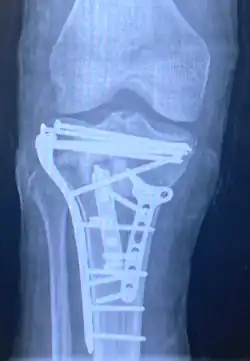

![]() | |

| A severe tibial plateau fracture with an associated fibular head fracture | |

Pain may be managed with NSAIDs, opioids, and splinting.[1][2] In those who are otherwise healthy, treatment is generally by surgery.[1] Occasionally, if the bones are well aligned and the ligaments of the knee are intact, people may be treated without surgery.[2] The surgery usually involves reducing the fractured fragments of the tibia plateau to their anatomical position and fixing them in place with screws only or fixed angle anatomical plates ensuring absolute stability. Implant selection is based on the type of injury. Generally, simple or incomplete fractures (Schatzker type 1) of the plateau are compressed with 6.5mm partially threaded cancellous screws. Complex type fractures will require a plate for enhanced stability. As the tibia condyles articulate with the femur (thigh bone) to form knee joint, any incongruity in the articular surface is unacceptable as it leads to early arthritis. Prolonged immobilization of the knee joint is also not recommended which result in stiffness of the joint and difficult recovery. Following a tibial plateau fracture, the patient is at risk for arthritis. This is referred to as post-traumatic arthritis. The more displaced the joint intra-articular surface is, the more likely post-traumatic arthritis is to occur. This occurs due to injury to the joint surface cartilage. When cartilage is damaged, arthritis can occur.[15] It's currently debated what role primary total knee arthroplasty (Joint Prosthesis) plays in the treatment of tibial plateau fractures. Although accompanied with risks small studies have shown promising results.[16]

Surgery

A tibial plateau fracture requires orthopaedic surgical intervention for treatment. After X-ray and CT scans confirm fracture, Open Reduction Internal Fixation (ORIF) with medial and/or lateral plateau fixation is done. There are 5 different approaches that are most commonly used.[3]